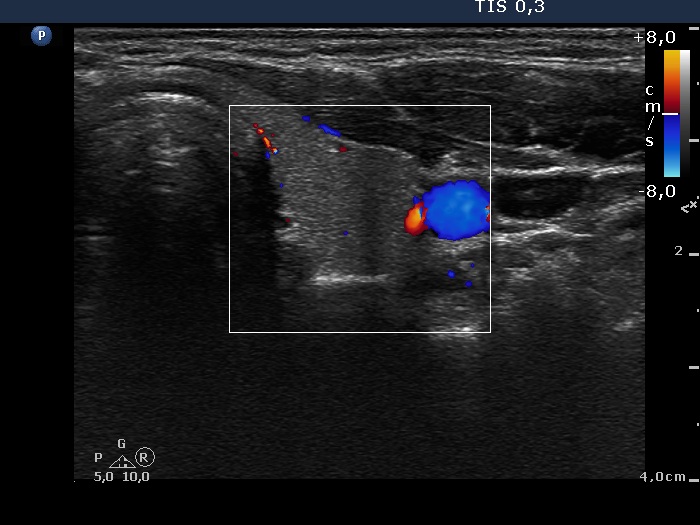

Third examination 24 months after initial investigation (3rd row of images)

Clinical data: The thyrostatic therapy was stopped 13 months ago. The patient had no complaints.

Palpation: unchanged.

Results of blood tests: euthyroidism (TSH 0.52 mIU/L, FT4 14.6 pM/L).

Ultrasonography: The size of the thyroid decreased further. The echo structure and the vascularization became normal.

Suggestion: to check the thyroid function every year, in the event of complaints or pregnancy at once.

Comment. This case demonstrates typical course of non-relapsing Graves disease. The change in hormone levels and in the ultrasound pattern are parallel.